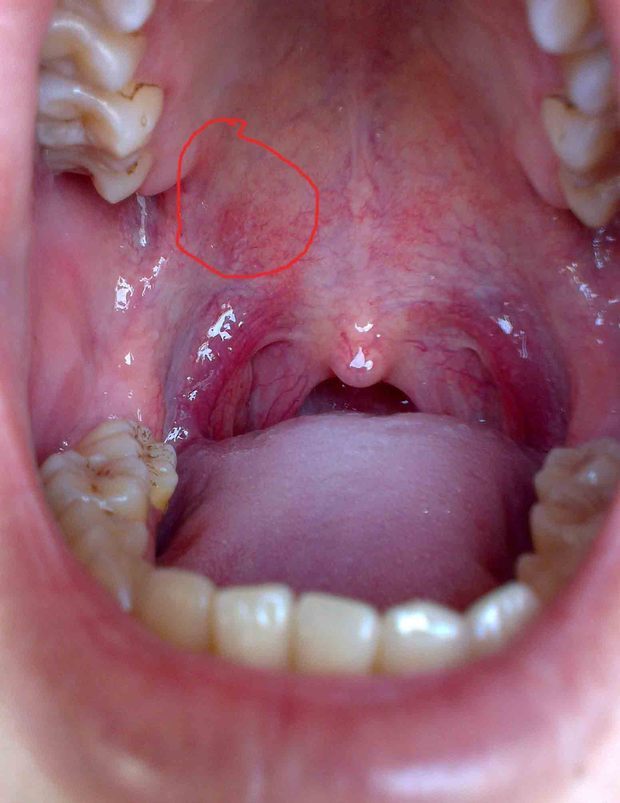

口腔上颚长个硬疙瘩大概一个月左右之前是上颚干疼特别是晚

有没有人知道我嘴巴里怎么回事,左边牙龈至上颚明显发白,牙龈很明显